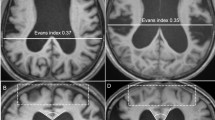

ITK-SNAP open-source software (v3.6.0-RC1; http://www.itksnap.org) was used to measure the lateral ventricular volume (LVV), which was determined using digital imaging and inference from patients’ medical images. According to the 3D thin-layer T1W imaging that contained the ventricles, we used the ‘freehand drawing style—polygon’ of the ‘polygon inspector’ modules to manually paint out the left and right lateral ventricles. After segmenting and modelling the ventricle, the volume information was calculated automatically (Fig. 3). Two independent operators (a radiologist and a neurosurgeon) measured the LVVs. The intraclass correlation coefficient for the LVV was 0.98.

Measurement of LVV and GFA maps of a typical iNPH patient and the reconstruction results of bilateral C_PH, left CST, and left TRP. (A) Measurement of LVV of a typical iNPH patient. Green and blue indicate the right and left lateral ventricles, respectively. (B, C, and D) GFA maps and reconstruction results of bilateral C_PH, left CST, and left TRP of a typical iNPH patient. (B) Colour bar from 0 (black) to 0.2 (white); red, purple, yellow, and green indicate the range of the right C_PH, left C_PH, left CST, and left TRP, respectively. (C and D) Reconstruction results of the bilateral C_PH, left CST and left TRP